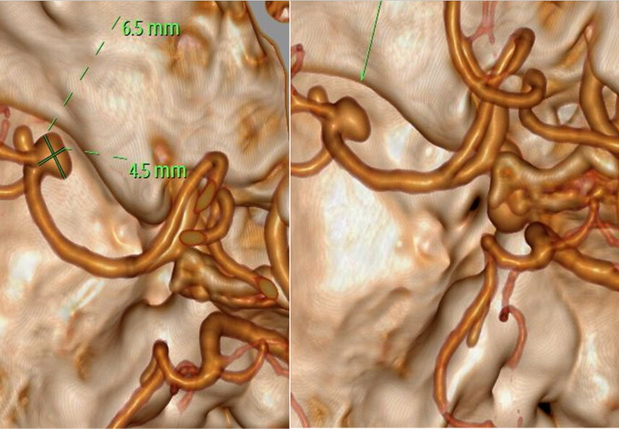

入院后,解先生完善了CT检查,影像可见蛛网膜下腔出血,以左侧外侧裂区域较为明显;左侧大脑中动脉M1段分叉处外缘及下缘各有一囊状凸起动脉瘤影,形态不规则,约6.5 mm×4.5 mm;DSA显示动脉瘤呈分叶状。